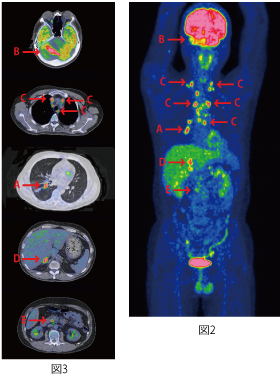

PET検査の画像は、図2と図3です。矢印Bが最初に発見された転移性脳腫瘍で、部位は右の小脳です。胸部中央(縦隔)から頸部にかけてのリンパ節に複数の集積が見られ(矢印C)リンパ節転移していることがわかります。原発のがんは矢印Aで示す右肺の下葉肺門の肺がんです。この方はさらに右副腎転移(矢印D)をしています。肺がんの遠隔転移としては脳転移、副腎転移が多く、この方はまさにその典型です。

さらにこの方の場合、重複がんとして、膵がんも見つかりました(矢印E)。これは肺癌の転移ではなく、膵がんとして新たに発生していて、しかも既に膵臓周囲のリンパ節にも転移しています。